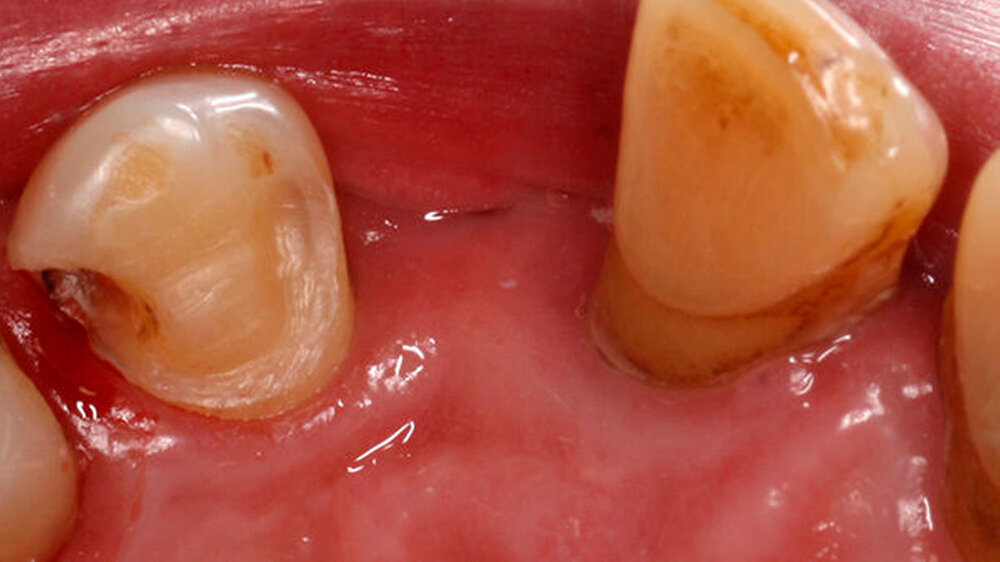

Für eine konventionelle brückenprothetische Versorgung scheiden die Schneidezähne ebenfalls aus: Zum langfristig prognostisch sicheren Ersatz des 22 wären Extraktionen und mehrere Substanz-opfernde Präparationen unausweichlich. Aufgrund des hohen Patientenalters und des Ausscheidens klassischer prothetischer Rehabilitationsmaßnahmen wird die Frontzahnlücke mit einer Adhäsivbrücke aus Metallkeramik versorgt (Abbildungen 3 und 4).

Durch die parodontal bedingte Elongation von 11 und 21 musste ein Kompromiss hinsichtlich der Gestaltung des Brückengliedes 22 im Hinblick auf dessen inzisale Ausdehnung erfolgen, so dass nun 23 kürzer ist als 22 (Abbildung 5). Ein halbes Jahr später befindet sich die Restauration unverändert in situ.